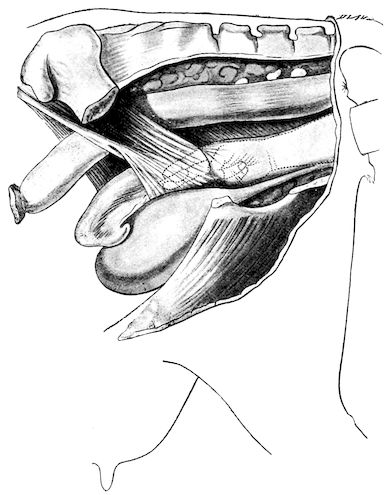

114. The fourth phase, or period of osteomalacia, i.e. softening of the bones, is also the last. It is rarely seen in large animals like horses and oxen, because accidents so often accompany the preceding stages and necessitate slaughter; but it is common in goats and pigs.

In this phase the bones become elastic, soft and depressible, yielding to the pressure of the operator’s fingers.

Fig. 4.—Deformity of the face in the horse shown in Fig. 2.

The flat bones are particularly liable to this change, which is common to domesticated animals. The bones of the head are the first to suffer; later those of the pelvis. The lower jaw becomes swollen, particularly about the centre of the branches which may attain three, four, or five times, their normal thickness.

The depression in the submaxillary space disappears. The upper jaw undergoes similar changes, becoming deformed and thickened until the cavities of the sinuses and the hollow appearance of the palate are lost, while the face is so changed that it cannot be recognised as that of a horse, goat, etc.

The molar teeth are almost buried, their tables alone being visible at the bottom of a depression, the edges of which rise above the neighbouring parts (pig).

Mastication is clearly impossible, the jaws appear paralysed, the muscles powerless, and only swallowing is possible, a fact which explains why life is only prolonged to this stage in animals which can be fed with a spoon or bottle (pigs and goats). The bones of the cranium, although greatly changed in texture, are always less deformed than those of the face.

The changes are such that it is often easy with a mere post-mortem knife to cut the head completely in two. Osseous tissue, properly so-called, has disappeared.

All the constituent tissues, with the exception of the skin and muscles, i.e., the bone, periosteum and aponeuroses, have the appearance and consistence on section of the fibro-lardaceous tissue seen in chronic inflammation.